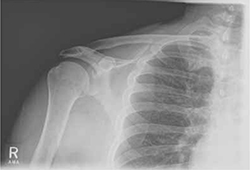

Rotator cuff tear was suspected because Robert had positive elements of the “rotator cuff triad”—supraspinatus weakness (as indicated by a positive empty can test), external rotation weakness (revealed by the French horn test), and a positive Hawkins impingement test. We ordered diagnostic studies, including plain radiographs, which revealed degenerative changes at the acromioclavicular joint, decreased acromiohumeral interval, and no significant changes at the glenohumeral joint (FIGURE 2), and magnetic resonance imaging (MRI) of the right shoulder. The MRI revealed a large, full-thickness rotator cuff tear of the supraspinatus tendon with retraction. A torn and retracted biceps tendon and AC joint osteoarthritis were also shown, likely causing a mass effect on the supraspinatus. The patient underwent surgery to repair the torn rotator cuff, with excellent results.

FIGURE 2

Chronic right shoulder pain

An AP view of the patient’s right shoulder shows acromioclavicular joint narrowing and degeneration and subtle narrowing of the acromiohumeral interval.